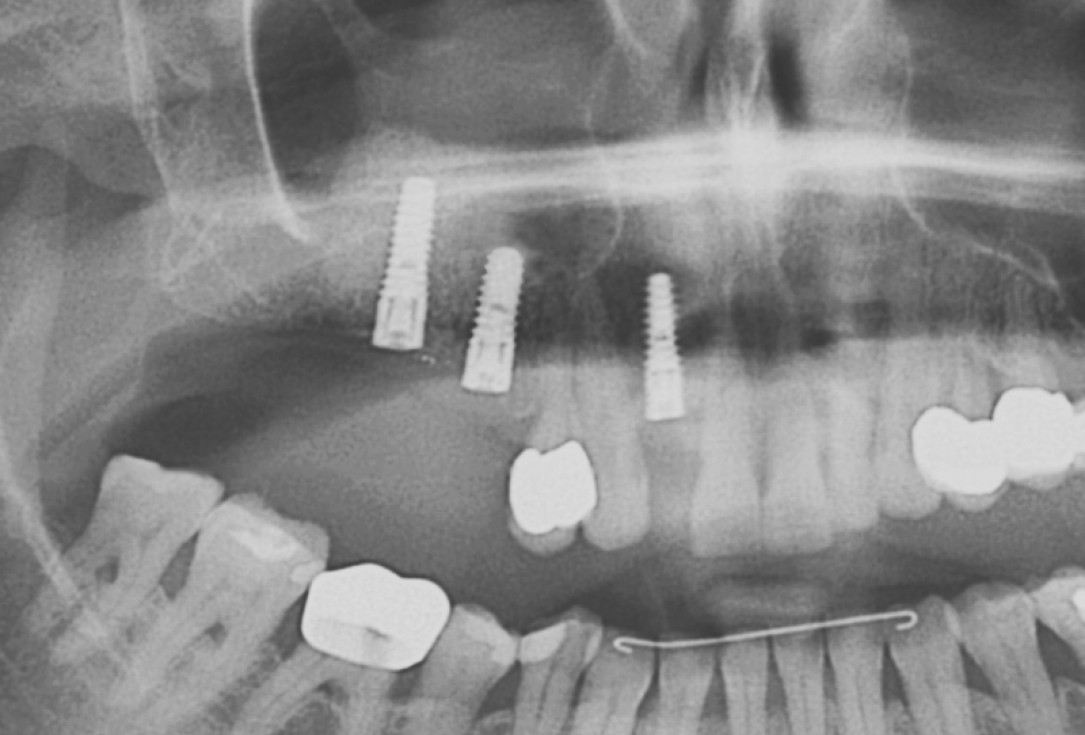

01/20 - Pre-operative x-rayGBR with maxresorb® & Jason® membrane - Prof. Dr. Dr. D. Rothamel

11/20 - Detail of OPG showing radiopacity of maxresorb®GBR with maxresorb® & Jason® membrane - Prof. Dr. Dr. D. Rothamel

20/20 - OPG showing stable placement of implantsGBR with maxresorb® & Jason® membrane - Prof. Dr. Dr. D. Rothamel